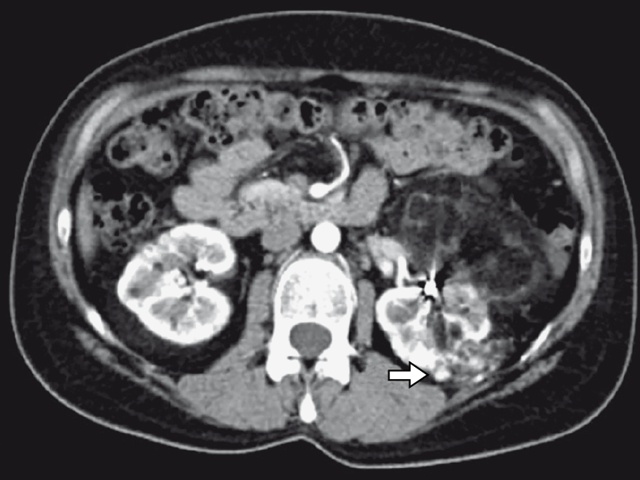

При МСКТ без контрастного усиления определяется солидное гетероэхогенное образование с четкими контурами, растущее из коры почки, с макроскопическим содержанием жира (достоверный признак жира – плотность ткани составляет – 10 HU или ниже). Также патогномоничным признаком является наличие «желобка» – АМЛ представляет собой треугольный или прямоугольный желобовидный дефект в коре. Для типичных АМЛ характерна гипоаттенуация (недостаточное ослабление излучения при КТ) (рис. 4–6). В то же время для АМЛ с низким содержанием жира характерна гетерогенная изоаттенуация и гиператтенуация, для АМЛ практически без жировых компонентов – гомогенная гиператтенуация.

Определяется характерное образование, исходящее из коркового слоя почки, желобовидной формы, неоднородное, с макроскопическим присутствием жира, плотностью около – 53 HU.